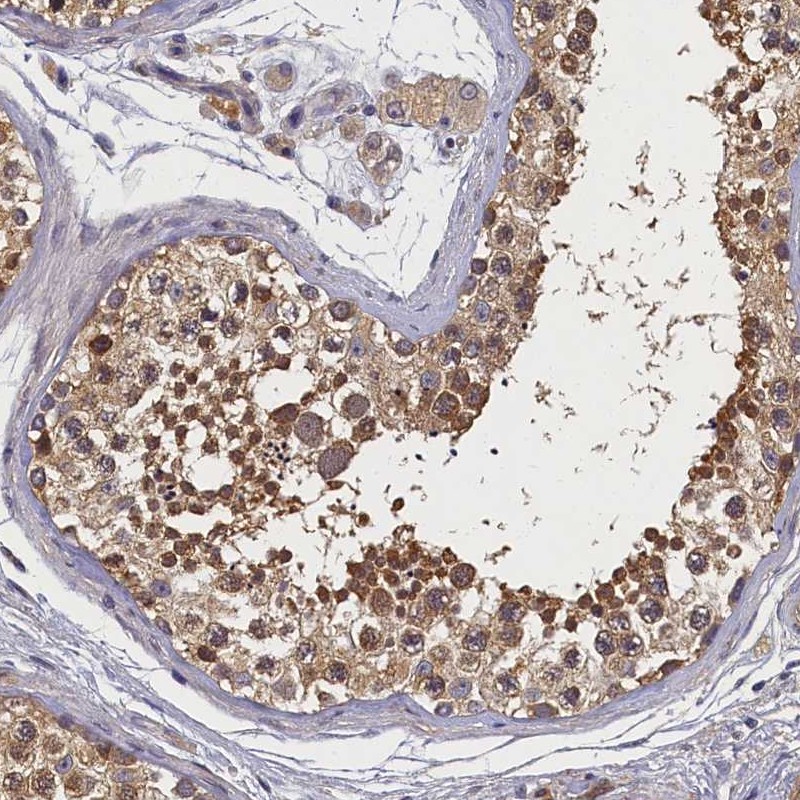

Immunohistochemical staining of human testis shows moderate cytoplasmic positivity in cells in seminiferous ducts and Leydig cells.